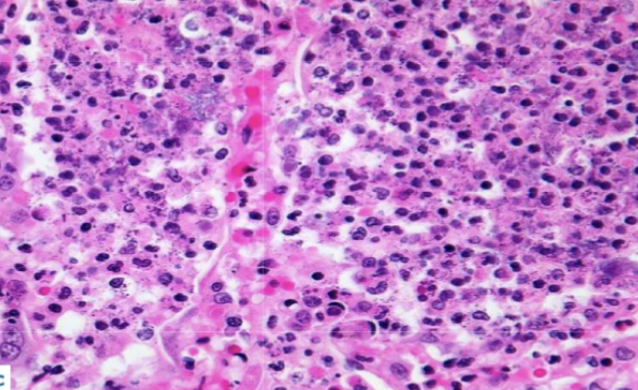

Giant cell myocarditis - Associated with thymoma, lymphoma, SLE, thyroidisits, dermatomysotis